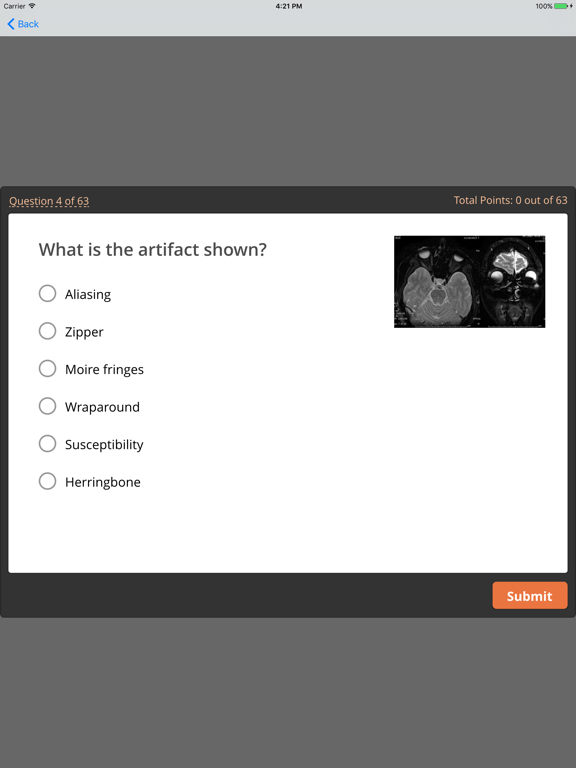

Radiology Core: Physics Plus

Lieu Duong

| 8 | Radiology Core: Physics Plus | 47 | 3.0 ⭐ |

Radiology Core: Physics Plus

MDToolkit

| 9 | Radiology Core: Physics Plus | 1.8K | 3.2 ⭐ |